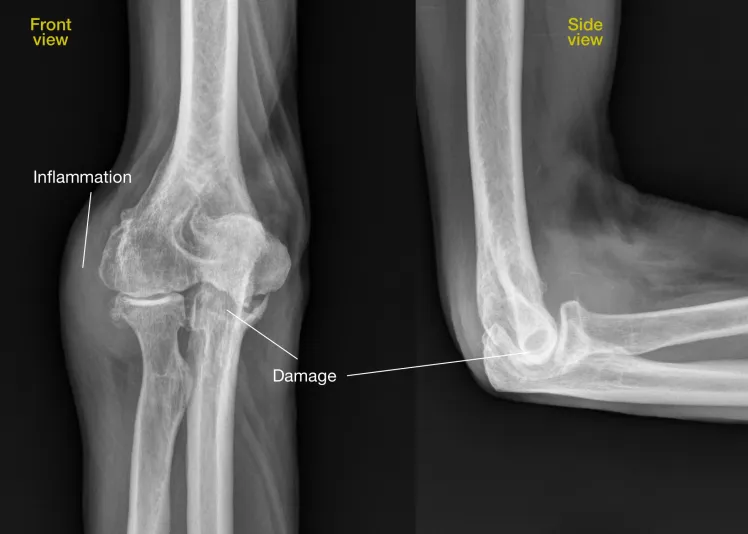

Διάγνωση

Η διάγνωση βασίζεται σε:

• Κλινική εξέταση από ορθοπεδικό.

• Ακτινογραφίες: δείχνουν φθορά χόνδρου, οστεόφυτα, στένωση αρθρικού διαστήματος.

• Μαγνητική τομογραφία: για λεπτομερή εικόνα χόνδρου, οστών και μαλακών μορίων.